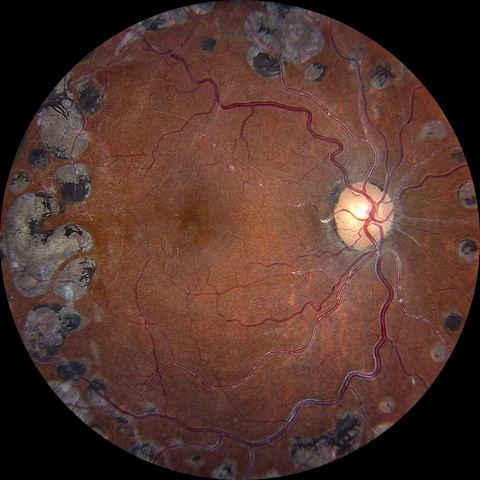

• Third Place – Meghan Menzel, CRA (Diabetic Scars)

Diabetic Scars